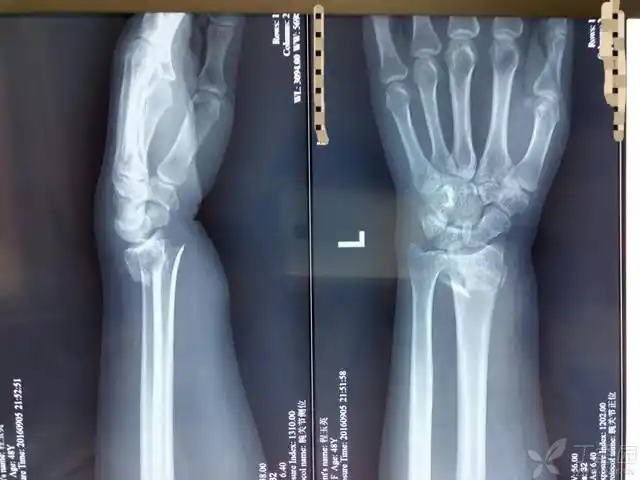

七旬老妪 散步滑倒 左手撑地 左腕剧痛 急至我院 尺桡双折 - 抖音

翻出了期间的各种片子,报告,开始研究,结果看到了手腕x光片的报告,尺

手腕关节的x线. 正常的. 否定.

x线片如下